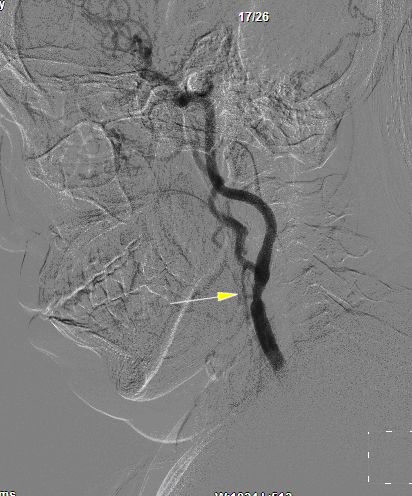

DSA:左颈内动脉85%狭窄,右冠状动脉狭窄约70%

患者女性,62岁,主因“发作性头晕伴右手麻木十余天”入院。入院后DSA显示:左侧颈内动脉重度狭窄。张勤奕教授于2011年10月31日为患者成功实施了左侧颈动脉内膜剥脱术,术后患者恢复良好,顺利出院。